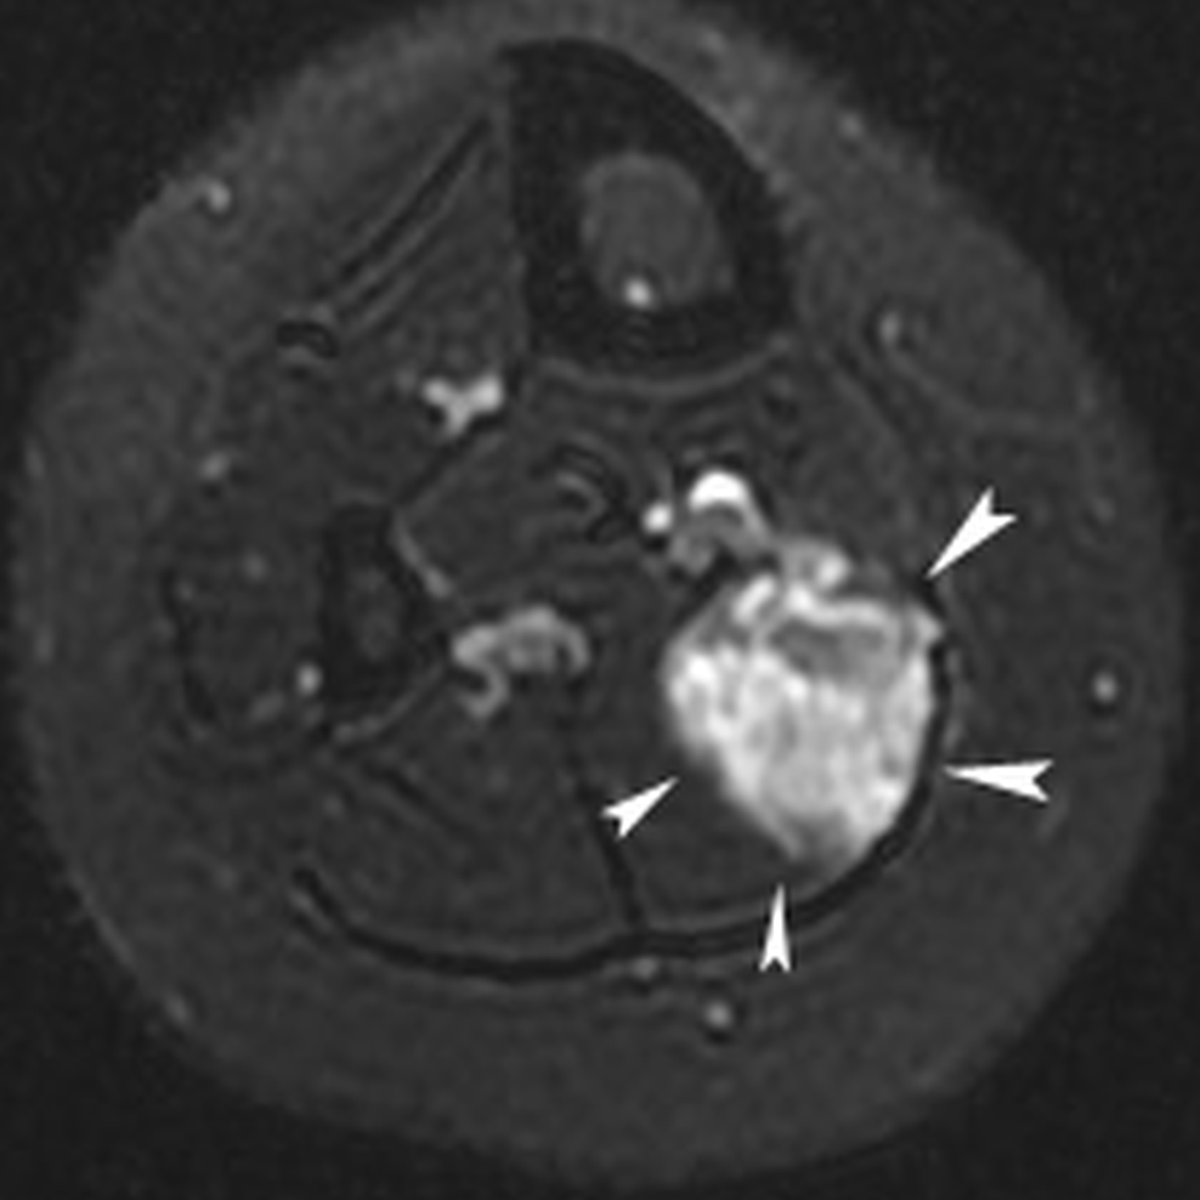

Figure 1a

Twenty-year-old female with chronic calf pain. T2-weigthed axial magnetic resonance image of the calf demonstrating an hyperintense mass lesion with a maximal diameter of 3.6 cm (white arrowheads) in the right soleus muscle, suggestive for low-flow vascular malformation.